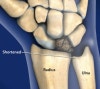

월상골(lunate)가 괴사되는 병으로 20~40세의 남성에서 호발하며 육체 노동을 하는 남자의 우성(dominant) 팔에 잘 생깁니다.

영상 검사

손목관절의 X-ray(PA, lateral) 검사를 시행합니다.

초기에는 월상골이 주위 손목뼈에 비해서 희어 음영이 증가되어 보이고, 진행되명 뼈의 괴사로 인하여 조각이 나고 붕괴가 되며, 결국에는 손목관절의 관절염 소견이 나타납니다.

무혈성 괴사 초기에는 방사선 골 주사나 MRI가 도움이 될 수 있습니다.